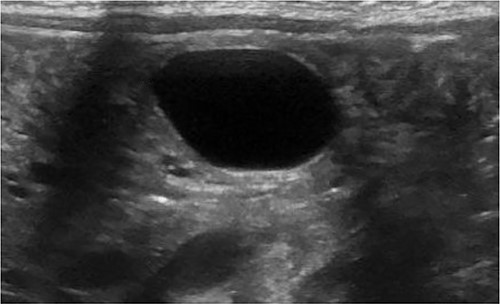

A 3.5 kg male was born via spontaneous vaginal delivery at 38 weeks. A chest radiograph demonstrated opacity at the medial right lung base (Fig. 1) consistent with the known congenital lung malformation. An abdominal ultrasound demonstrated a simple cyst with a gut signature consistent with an enteric duplication cyst (Fig. 2).